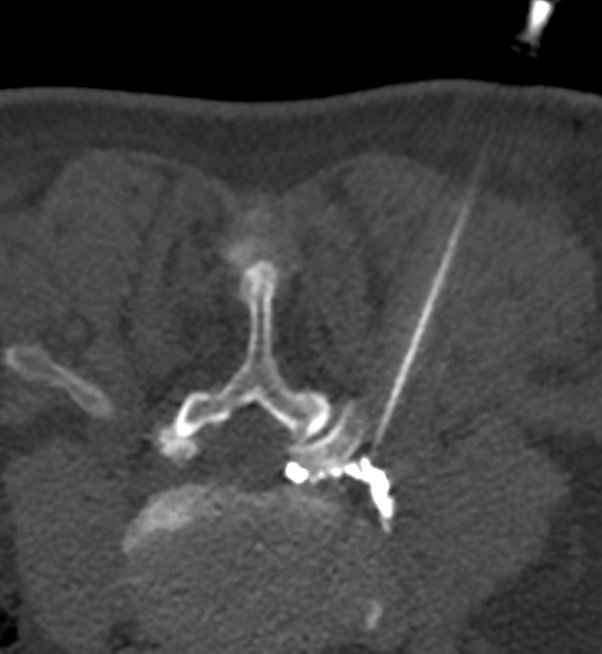

A CT-guided lumbar spine injection is a procedure used to deliver medication directly to the spine to treat pain, inflammation, or nerve irritation in the lower back. This injection can target different areas depending on the condition being treated, including:

Nerve Block: Used to target specific nerves, providing pain relief and helping to pinpoint the source of pain.

Epidural Injection: Aimed at reducing inflammation and pain in the epidural space, often for conditions like herniated discs or sciatica.

Facet Joint Injection: Focuses on the facet joints in the spine, often used to treat arthritis or joint-related pain in the lower back.

CT-Guided Lumbar Injections

Nerve Block/Perineural

Nerve blocks, also known as perineural injections, are used to target specific nerves that are causing pain, inflammation, or discomfort. This procedure is frequently used to treat conditions such as neuralgia or radiculopathy.

Epidural

An epidural injection is used to deliver medication directly into the epidural space of the spine. The procedure is commonly performed to treat chronic back pain caused by conditions such as herniated discs, spinal stenosis, or sciatica.

Facet Joint

Facet joint injections are used to treat pain originating from the facet joints in the spine, often caused by arthritis or degeneration. This can provides pain relief and reduces inflammation within the facet joint.